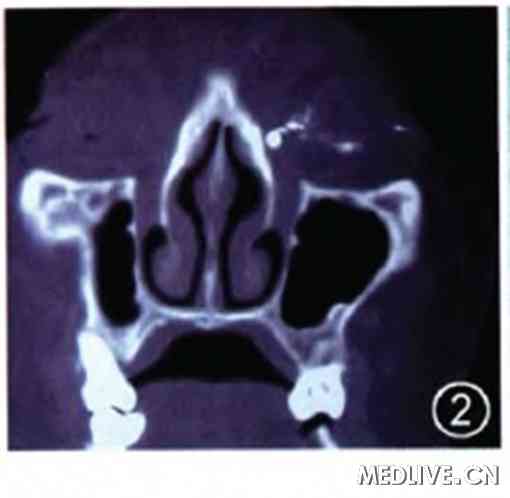

从下泪小管向泪道内注入碘化油注射液后行泪道CT水平位加三维重建检查,结果提示:左侧泪囊窝造影剂存留,上下泪小管和副泪小管区域有多个点状钙化影(图2)。

图2 先天性副泪小管患者左眼泪道cT检查图像,可见泪小管有多个高密度影,考虑部分为结石点状钙化影,部分为造影剂显影

多余的泪小管属于泪器先天异常,又称为副泪小管。查阅相关文献,国内有过少量关于先天性多泪点和多泪小管(副泪点和副泪小管)的文献报道,所报道的副泪点往往开口于正常泪点附近,而开口在泪阜部的先天性副泪小管者至今尚未见报道。本例患者经过详细查体、辅助检查结合术中探查,先天性副泪小管开口于泪阜部得以确诊,并且患者副泪小管及上下泪小管和泪囊中均存在大量的细沙样结石。至今泪石的起源尚有争议:有人认为是由于泪膜中细菌的存在或慢性炎症与含有高浓度钙和磷的泪水,共同促使泪石的形成,甚至诱发泪囊炎;也有人认为一些异物如睫毛作为蛋白和细菌的吸附物,形成大量的泪石结晶。影像学表现:X线平片诊断意义不大,含钙质多的结石可见斑点,致密小片状,泪道造影可显示泪道狭窄、阻塞,狭窄以上扩张,扩张的泪囊或憩室内有结石充盈缺损。本例患者泪道CT冠状位检查结果显示泪小管区域有多个点状钙化影,系结石显影的可能性大。当然,因为本例患者泪道内已经注入显影剂碘化油,所以部分点状高密度影也可能是碘化油的显影。